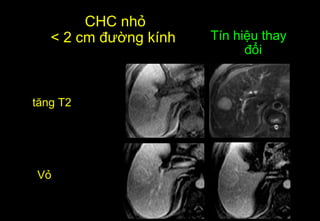

CHC nhỏ

< 2 cm đường kính

Vỏ

Tín hiệu thay

đổi

tăng T2

CHC nhỏ < 2 cm